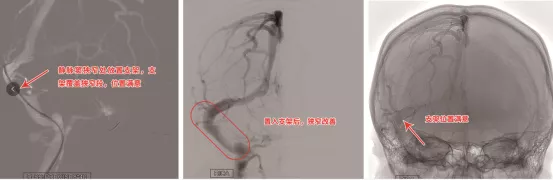

輾轉多家醫院,診療效果也都收效甚微。經多方打聽,小吳及家人來到首都醫科大學三博腦科醫院神經介入科尋求治療。以往影像檢查顯示:左側橫竇—乙狀竇交界段及右側乙狀竇管腔不規整伴充盈缺損。劉加春主任根據患者的症狀、體徵及檢查結果診斷為顱內靜脈竇狹窄。

患者顱內靜脈竇細線樣改變導致整體血流速度明顯延遲,這是導致患者長期顱內壓增高的病因,這也是患者反覆頭痛及視力模糊的罪魁禍首。

經過全科討論,認為要根本解決患者的高顱壓,應該透過血管內介入治療來改善患者的靜脈引流通路。在患者及家屬的同意下,在麻醉科的全力配合下,劉加春主任帶領團隊在全麻麻下經股靜脈逆行造影,並使用靜脈壓力導絲測壓,發現患者靜脈迴流差,右側的橫竇為優勢引流,左側橫竇—乙狀竇交界段及右側乙狀竇都存在重度狹窄,壓力差遠遠超過10mmHg,手術治療指徵明確。

隨後靜脈竇狹窄擴張成形及支架置入術。這是一項難度較高的血管介入手術,因為顱內靜脈竇重度狹窄,甚至有的血管還呈九曲連環狀,要將支架準確無誤地放在靜脈竇狹窄處非常困難,稍有不慎便會造成患者血管損傷,乃至生命危險。劉加春主任決定在左側左側橫竇—乙狀竇交界段行球囊擴張成形術,在右側的優勢引流血管——右側乙狀竇行支架置入術,既保證患者效果,也為患者減輕經濟負擔。

術中,劉加春主任準確無誤地定位病灶後,嫻熟地操縱著微導絲,先沿著微導絲將球囊擴開左側橫竇及乙狀竇狹窄段,造影顯示狹窄部分改善。再沿著微導絲將球囊擴張右側乙狀竇處,再送入支架,最後精準地釋放在狹窄段,撤出釋放裝置後再次造影可見狹窄解除, 支架貼壁良好,狹窄的靜脈竇便得以充分開啟。再次用壓力導絲測壓,各靜脈竇無明顯壓力差,證實手術有效地解除了靜脈迴流障礙。術後,小吳也感覺頭痛、頸痛較術前明顯緩解,視力也較前有所恢復。術後第5天的腰穿測壓也證實,小吳的顱內壓已經降下100mm多水柱。